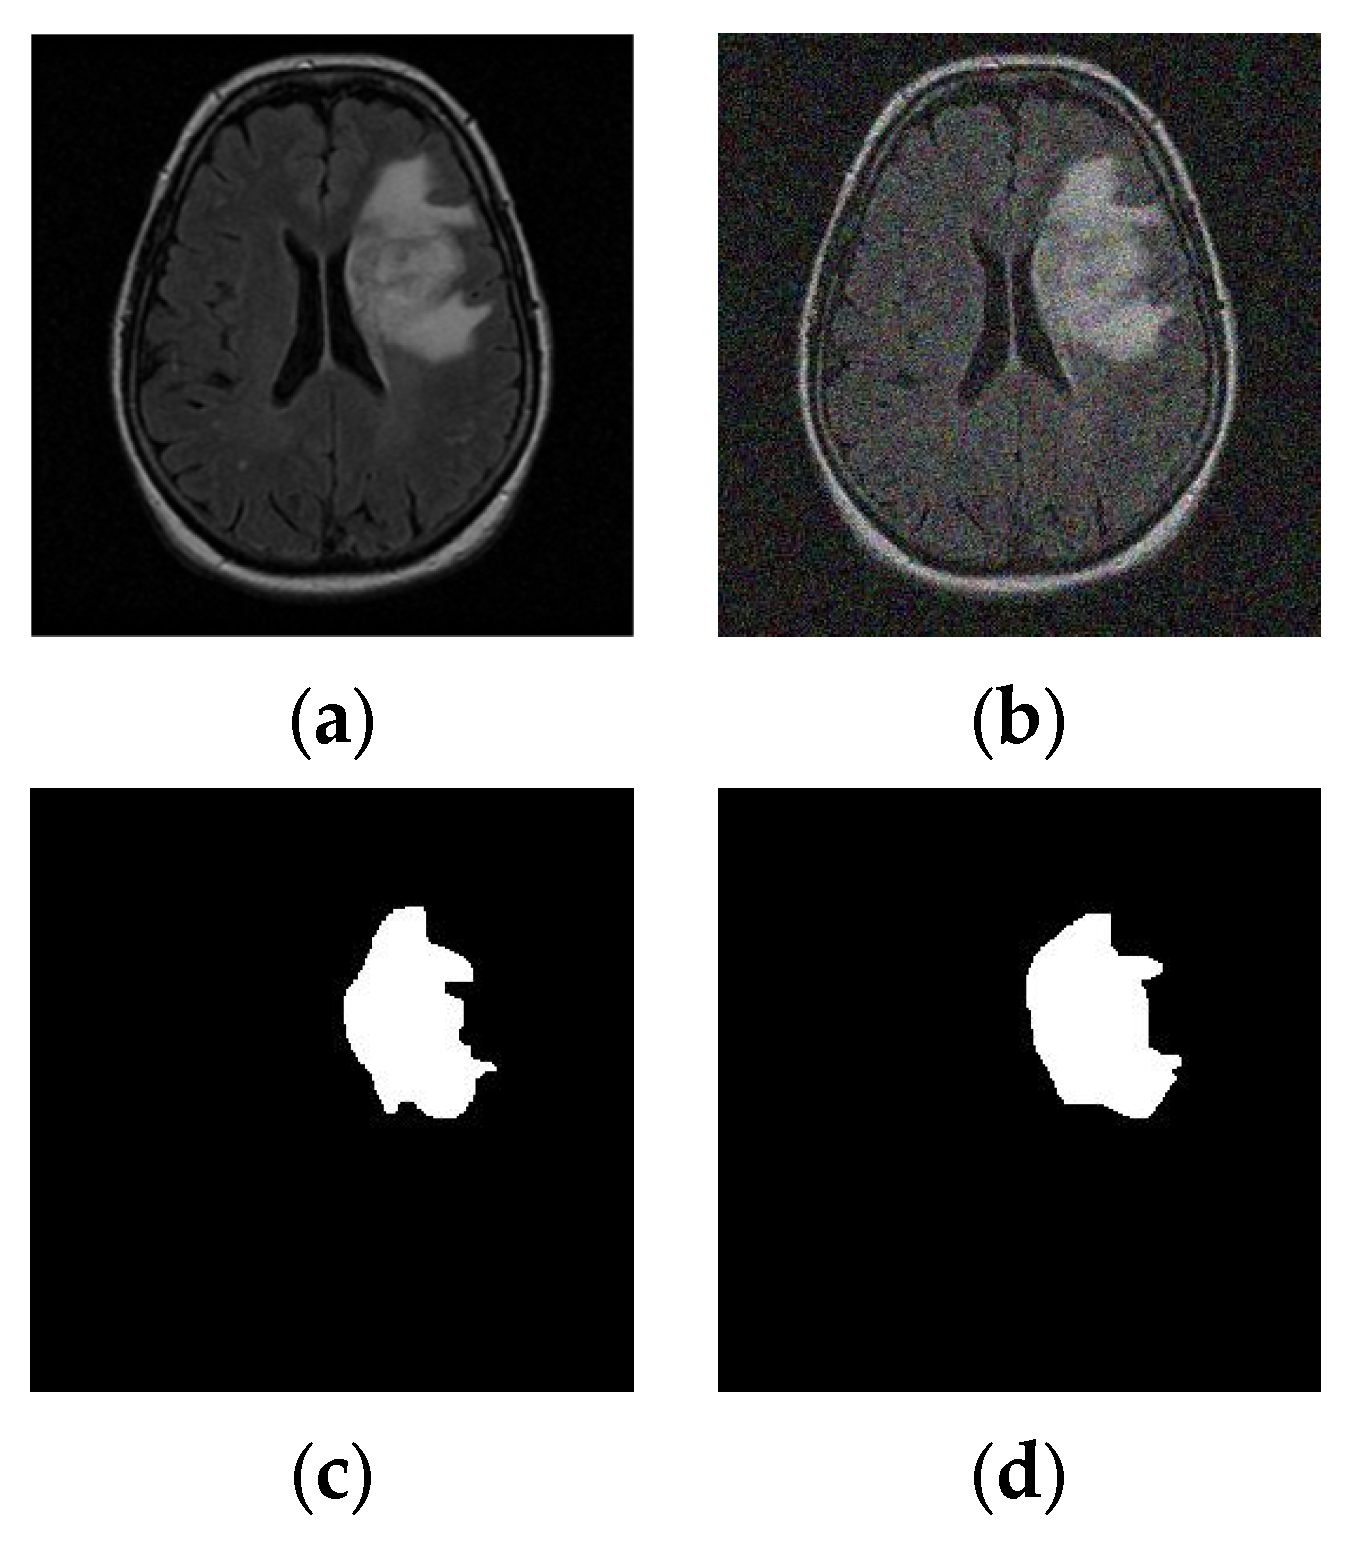

3.2. MRI Dataset